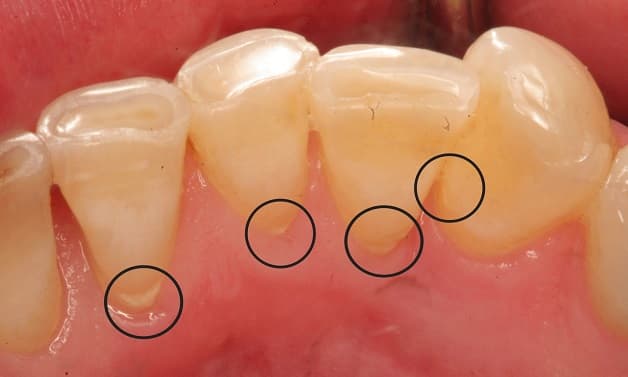

Cao răng không phải là vấn đề hiếm gặp trong đời sống. Thậm chí, không nhiều người có thể tránh gặp hiện tượng này. Cao răng là sản phẩm của hiện tượng các mảng bám quanh răng bị vôi hóa bởi các muối vô cơ canxi photphat khi kết hợp cùng vụn thức ăn, axit, nước bọt, vi khuẩn và các yếu tố khoang miệng. Cao răng có màu đậm dần theo thời gian, có thể xuất hiện với màu vàng ngà, nâu đỏ hoặc màu đen nên thường khá dễ nhận biết.

Cao răng là hiện tượng rất dễ bắt gặp trong đời sống hằng ngày